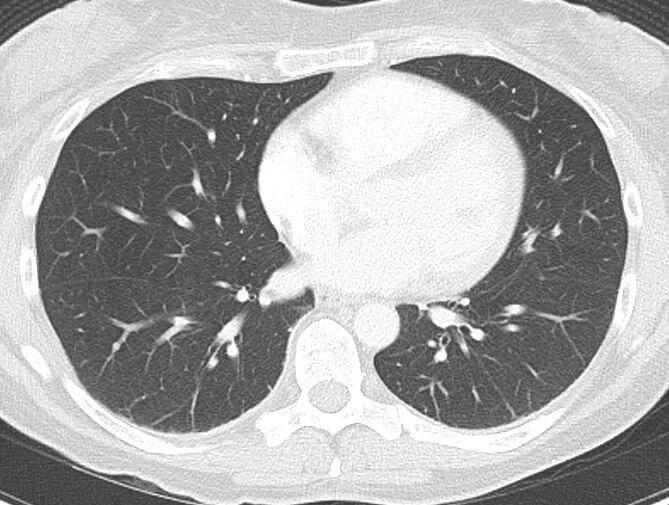

Have you been referred for a breast biopsy? Has your mammogram showed a suspicious lesion? Visit http://www.xraypmb.co.za/s/Image-guided-breast-biopsy-short… to learn more about how we do image guided breast biopsies.